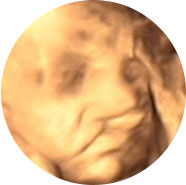

四维彩超能多方位、多角度、立体显示胎儿生长发育情况,为早期诊断胎儿先天性体表畸形如唇裂,脊柱裂,大脑、肾、心脏、骨骼发育不良等,和先天性心脏疾病提供全面的科学依据。

唇腭裂